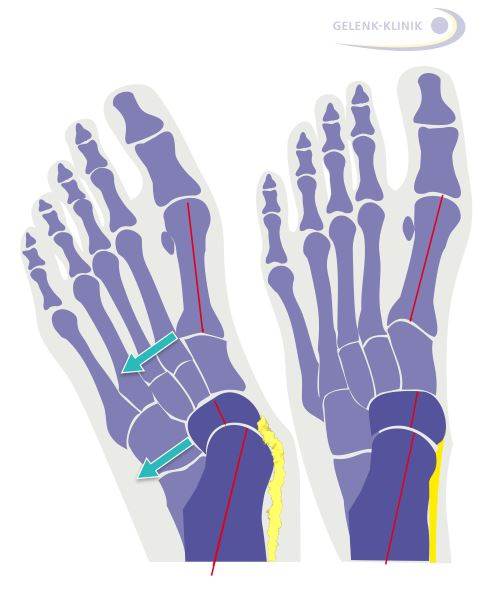

Evans-Osteotomie: Fußbegradigung durch knöcherne Korrektur

Ziel dieses Eingriffes ist es, den Fuß zu begradigen. Um eine Chance auf eine langfristige Korrektur zu haben, müssen die Zugverhältnisse und Weichteilspannungen der Fußwurzel verändert werden. Der Weichteileingriff an der Tibialis-posterior-Sehne kann dies praktisch nie alleine erreichen. Über einen Schnitt im äußeren Bereich des Fersenbeins (Calcaneus) bringt der Arzt einen Knochenkeil z. B. aus dem Beckenkamm ein. Diese Operation korrigiert die Stellung von Vor- und Mittelfuß gegenüber dem Sprungbein (Talus).

Verschiebungsoperation des Fersenbeins

Die knöcherne Verschiebung des Fersenbeins (Mediale Displacement Osteotomy, MDO) ist geeignet, die Fehlstellung des Rückfußes auszugleichen und korrigiert vor allem die Knickfuß-Komponente. Durch die Verlagerung des Fersenbeins nach innen verändert sich auch die Zugrichtung der kräftigen Achillessehne. Dies richtet den Fuß insgesamt auf.

Die Fehlstellung des Fersenbeins verändert die Zugwirkung der starken Achillessehne: Sie wird beim Gehen nicht ausreichend gedehnt und verkürzt sich daraufhin. Diese Verkürzung spielt eine wichtige Rolle beim Aufrechterhalten der Knick-Senkfußfehlstellung. Eine Normalisierung der Fersenstellung verhindert die fortschreitende Verkürzung der Achillessehne.